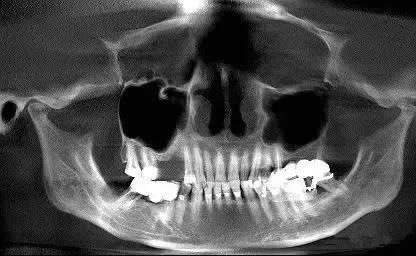

第二圖:上頜竇氣化,導(dǎo)致上頜竇很大,骨高度不足,但是上頜竇底平,粘膜很干凈。適合外提升或者高手可行內(nèi)提升。(還有二次內(nèi)提升)。